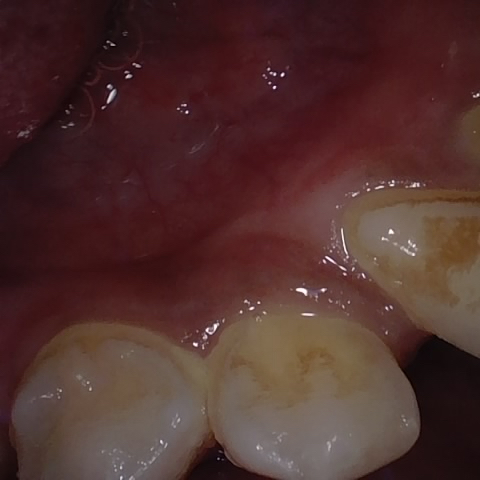

Annotated as "Good"